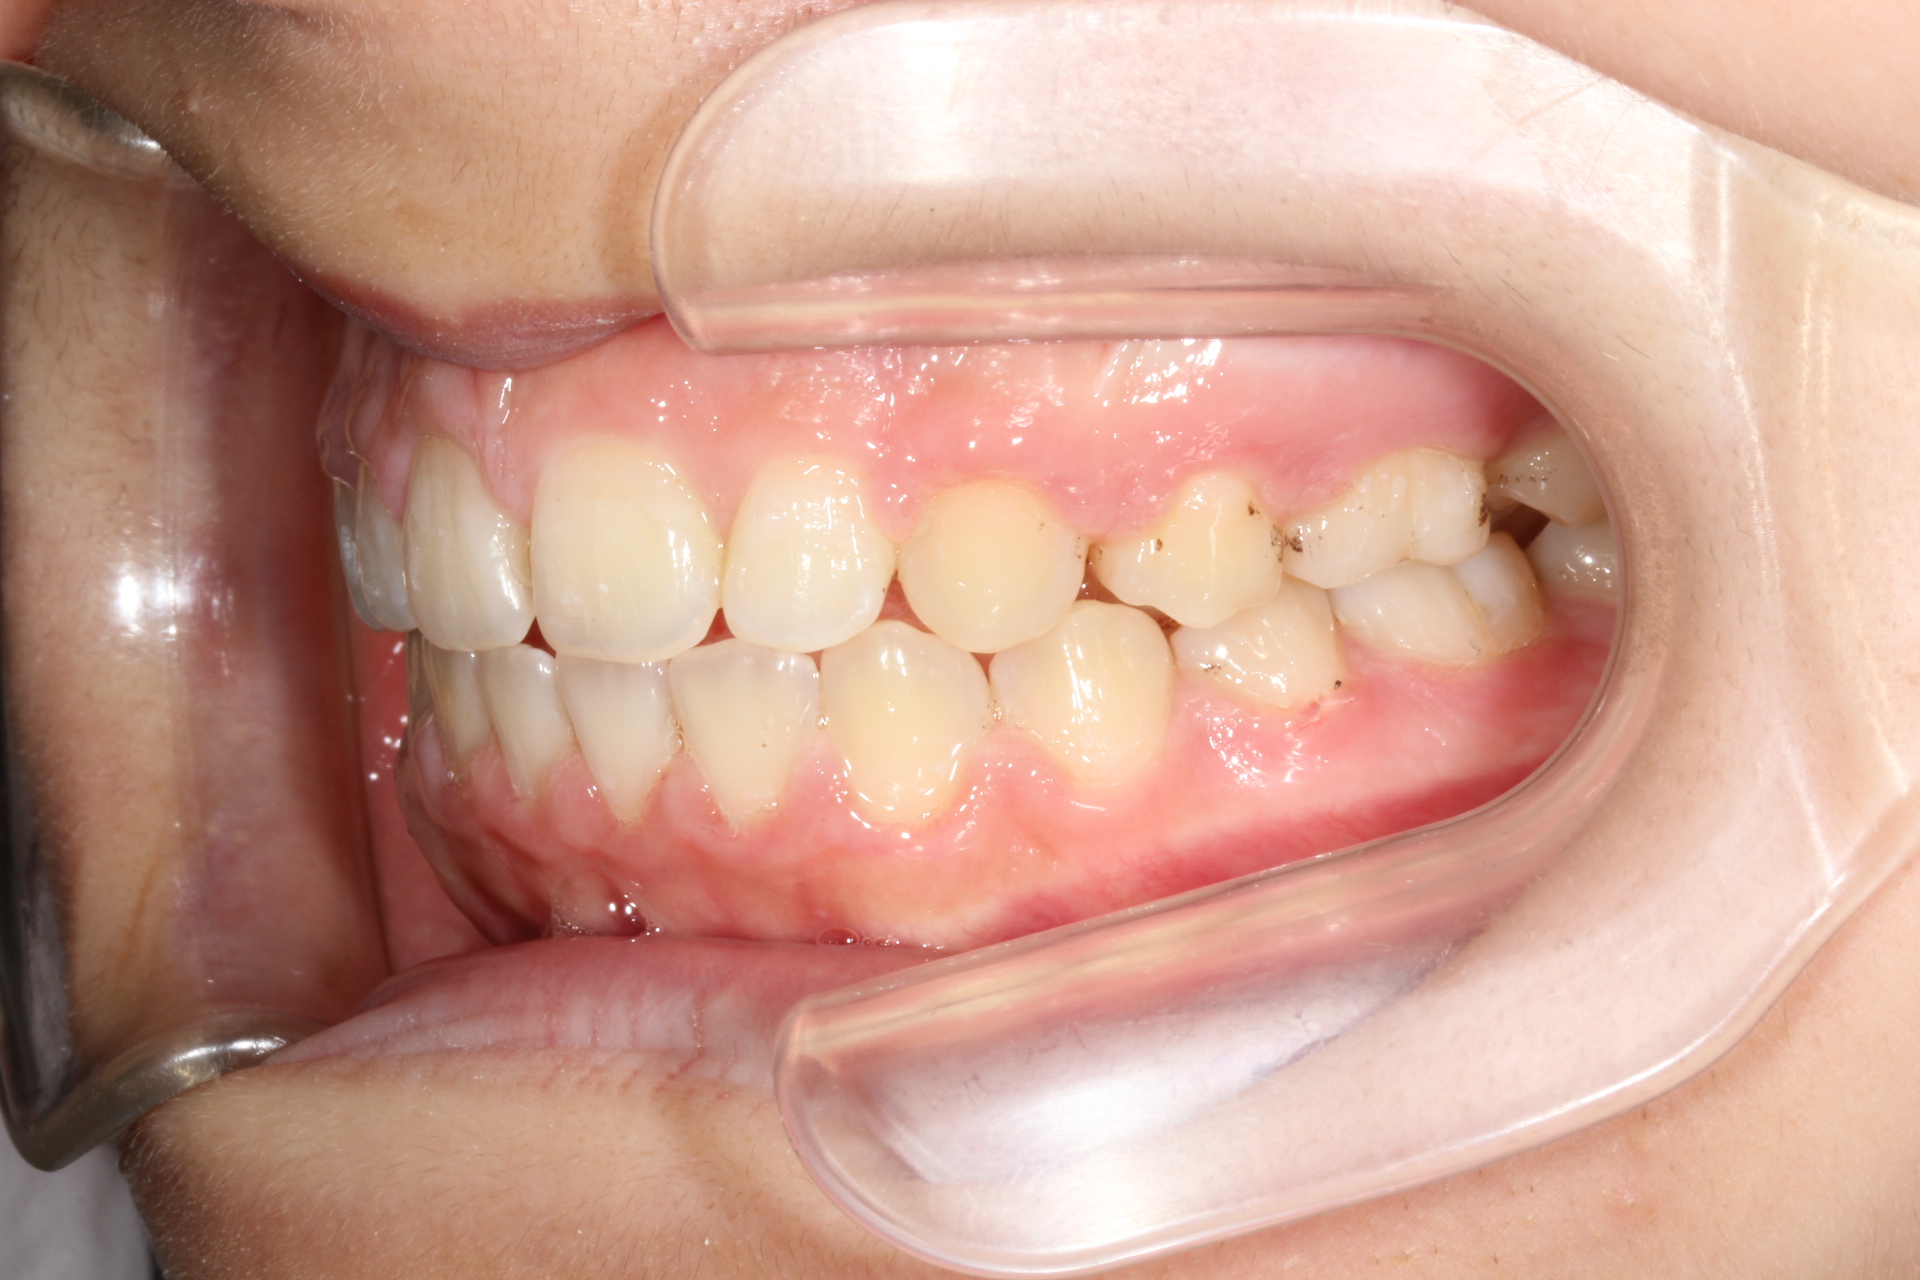

10代女性。 主訴は「上の歯が出ていて気になる」。

臼歯関係がFull classⅡで上顎前歯の唇側傾斜と側貌の前突感の改善のため、上顎左右側第一小臼歯を抜歯してマルチブラケットにて咬合関係の改善を行なった。動的治療期間は16ヶ月。上顎前歯の唇側傾斜が改善され良好な咬合関係が得られている。

ブラケットが粘膜に当たり口内炎の可能性あり。歯牙移動時の疼痛あり。上顎前歯の移動量が大きいことから歯肉退縮及び歯根吸収の可能性あり。